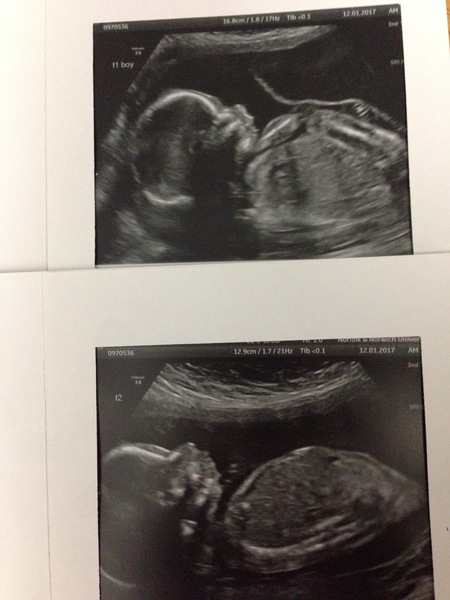

phoebe2016 · 10/01/2017 06:25

We had our sexing scan last night and are having a little girl! Sooo happy! Gringot some great pics printed off, a dvd of the scan, and a usb stick with 23 pics on, all for £35!

Forgot to add a pic! Bubba was very active, saw her opening her mouth, wriggling around like mad and sliding down the uterus, was lovely!